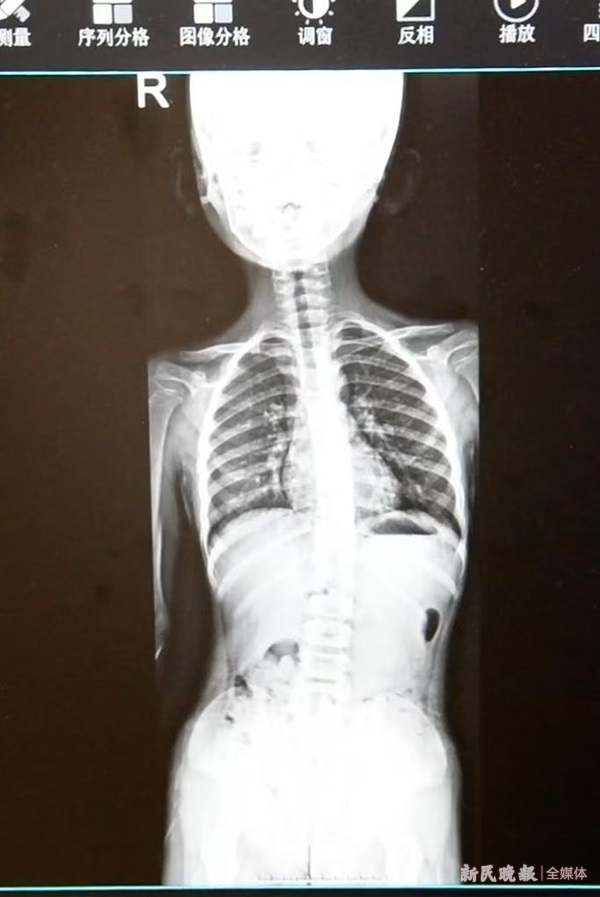

“站没站相、坐没坐相”“写作业老歪着头”“肩膀一高一低”你是否经常这样描述自家孩子的体态? 暑假里,前来医院就诊和咨询脊柱侧弯的患儿数量明显多了起来。上海

“站没站相、坐没坐相”“写作业老歪着头”“肩膀一高一低”你是否经常这样描述自家孩子的体态? 暑假里,前来医院就诊和咨询脊柱侧弯的患儿数量明